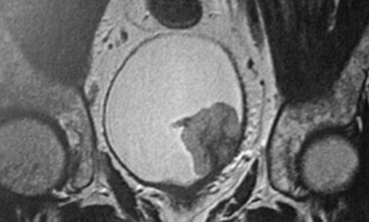

Vous hospitalisez le patient et mettez en place un monitoring cardio-tensionnel et un traitement associant insuline-glucose par voie intraveineuse (IV) et bêta-2 mimétique en aérosol. Vous réalisez une échographie qui retrouve une dilatation pyélocalicielle du rein gauche (image ci-contre), ainsi qu’une radiographie de thorax qui retrouve une surcharge modérée. La biologie de contrôle retrouve une kaliémie à 4,7 mmol/L et une créatininémie à 627 μmol/L.